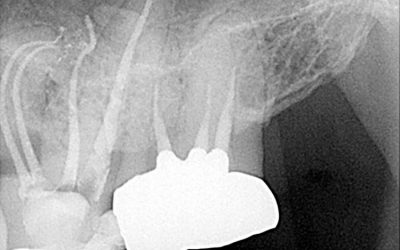

CASE STUDY: Coronal minimally invasive access

View all the X-rays & Case Photos. Case completed using Bassi Logic™ 25/.03 and 30/.05